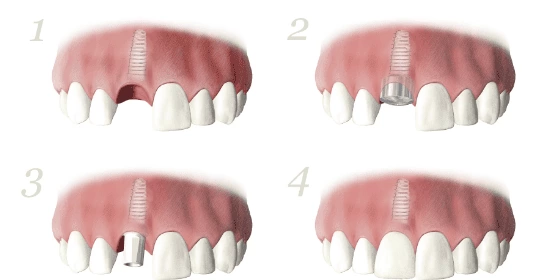

人工植牙療程

- 將OSSEOTITE植體植入齒槽骨中

- 鎖上癒合基座使牙肉成形

- 當植體穩固在齒槽骨中,就可接上假牙基座

- 最後的步驟即是接上牙冠,也就是假牙